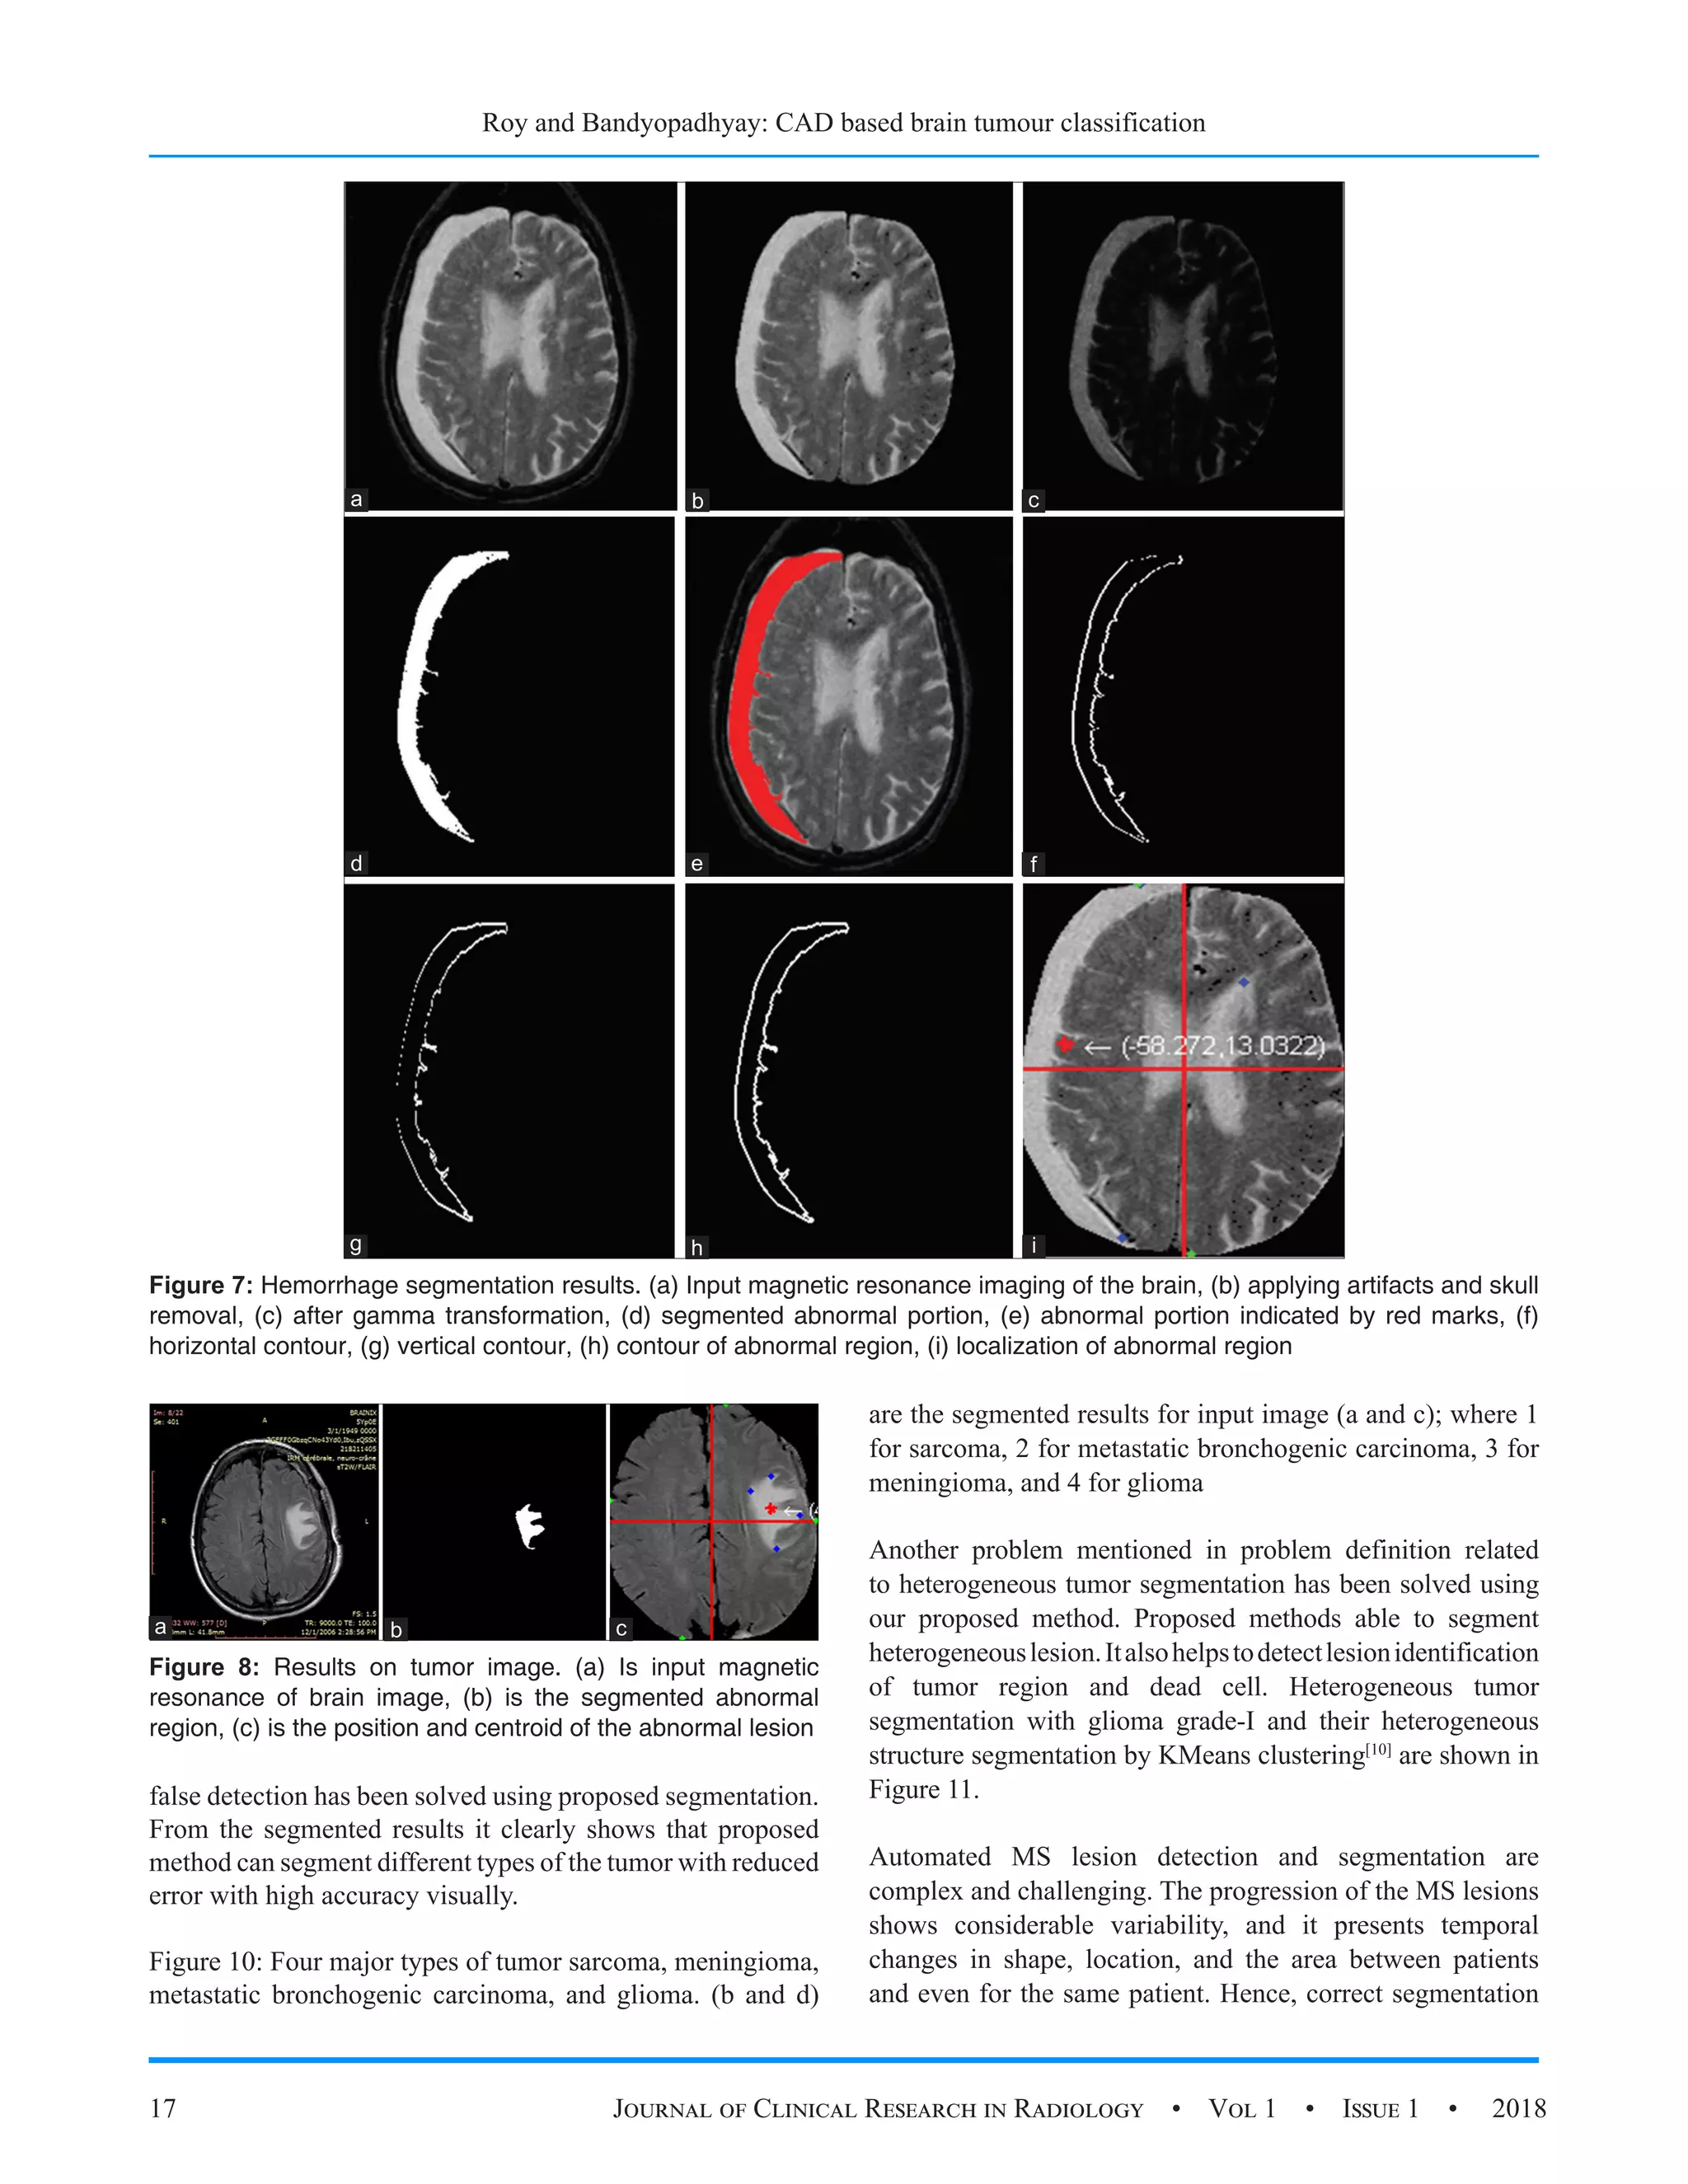

Figure 7: Hemorrhage segmentation results. (a) Input magnetic resonance imaging of the brain, (b) applying artifacts and skull

removal, (c) after gamma transformation, (d) segmented abnormal portion, (e) abnormal portion indicated by red marks, (f)

horizontal contour, (g) vertical contour, (h) contour of abnormal region, (i) localization of abnormal region

to achieve the same. For brain hemorrhage segmentation,

several steps have been proposed, and details are shown in

Figure 7.

Figure 8: Results on tumor image. (a) Is input magnetic

resonance of brain image, (b) is the segmented abnormal

region, (c) is the position and centroid of the abnormal lesion

regions. It improve diagnosis quality. Figure 8 shows that

the output of the proposed methods describes earlier test on

image standard dataset.[10-12]

Here, the segmented abnormal regions and location of the

abnormal regions are clearly visible in the output as shown

in Figure 8. Proposed methodology tested on both normal

and abnormal tumor images, and segmentation reduces false

detection for normal regions image. Another two MRI of the

brain images with segmented abnormal lesion and location

of the abnormal lesion with heterogeneous natures are shown

in Figure 9.